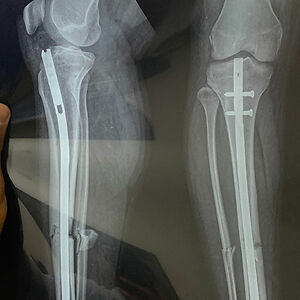

Had a male in his 50s WALKS into trauma to have his left thigh stitched up. Not an uncommon wound in an agricultural area. Speaking to him while stitching him up he tells me he fell off a ladder while cutting a branch and the machete sliced him on the way down. Told him I was going to write him up for an xray of the entire leg just in case. He kept on saying he was fine, his knee hurt a bit but logically that was from the fall, I agreed, but asked him to go to the xray department just in case. He reluctantly walk there and back. X-rays showed a helical fracture almost the entire length of his femur! Besides being a dangerous fracture the femur is supposed to be the most painful bone to break and he was walking around. In the end had to show him the break to get him to sit down on a wheelchair and into the hands of orthopedics. That man's pain tolerance still impresses me.